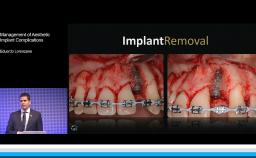

This lecture provides evidence to show that biological risk cannot be prevented, only reduced, for dental implants in periodontally compromised patients. Contrary to prior understanding, full-mouth tooth extraction does not result in eradication of all periodontopathogens but rather in their severe reduction. Literature is presented to show that the microflora in periodontally compromised patients does not significantly improve over time, even years after extraction. This lecture shows that implants should be considered only for periodontally compromised patients exercising sufficient oral hygiene measures and receiving adequate supportive periodontal therapy. Additional key factors for stable long-term results are presented, including a good soft tissue seal and free gingival grafts to facilitate oral hygiene procedures.